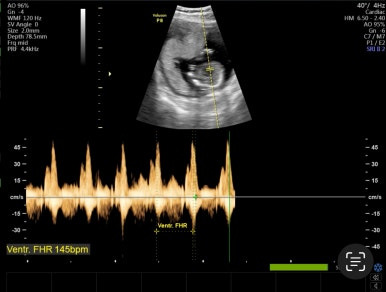

25주 1일

일반 정기 검진으로 태아의 성장을 점검하고 특이사항이 없으면 다음 검진 때 간다.